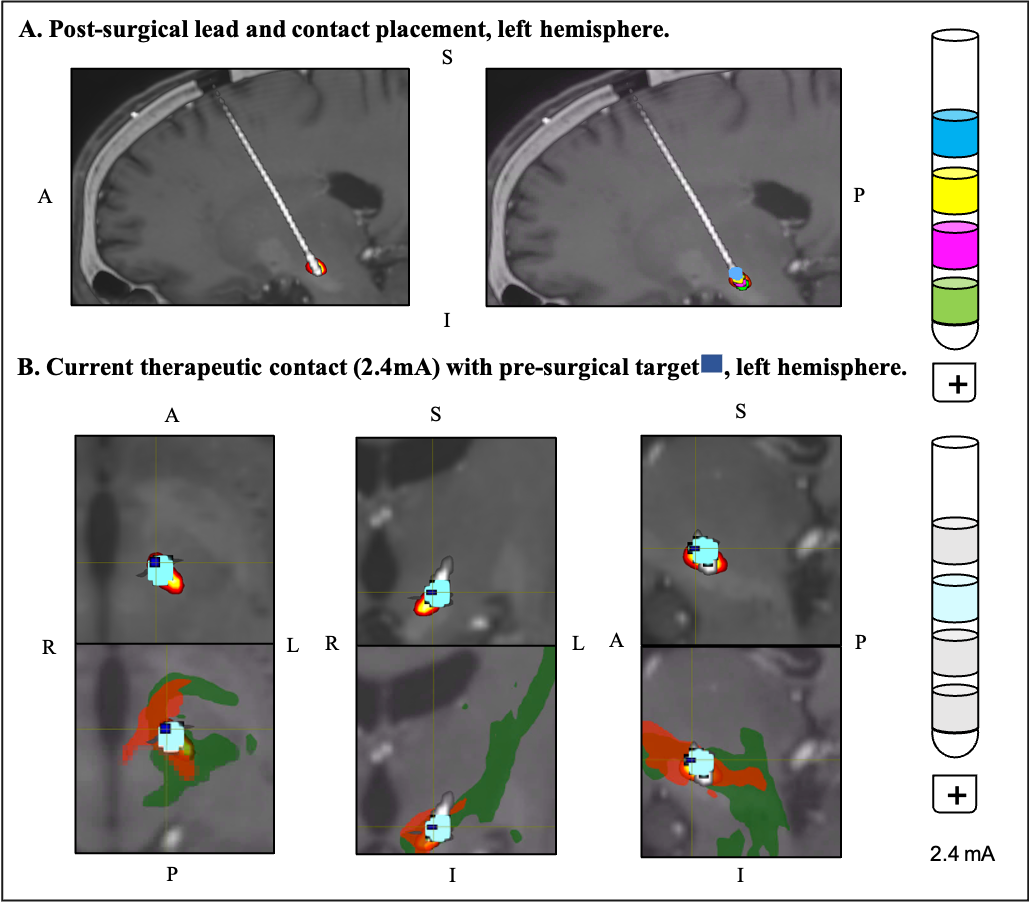

Results: We were able to plan a surgical target at the intersection of the motor and vmPFC pathway, Fig 1. Post-surgical assessment of the electrode placement showed that the initial target was stimulated with the current therapeutic settings (Fig 2B). The patient reported a substantial reduction in apathy symptoms, along with an 81% decrease in medication use with these settings (ON med, ON stim). At the 6-month follow-up, there was a 6-point reduction in the SAS (from 21 OFF med to 15 OFF med/ON stim, -29%) and a 20-point improvement on the MDS-UPDRS III (29 OFF med to 9 OFF med/ON stim, -69%).

Fig 2.